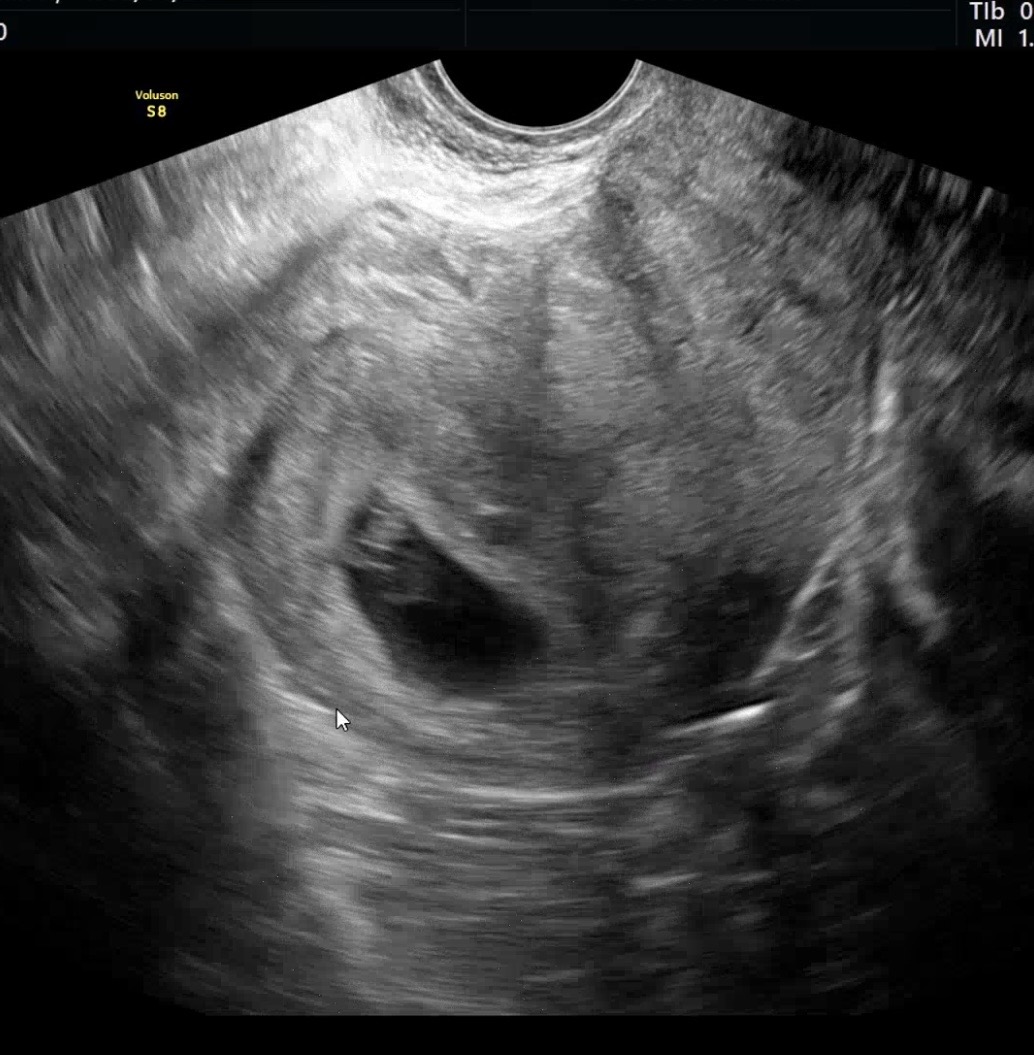

| 가슴 떨리는 임신 이야기를 공유해 주세요. | 이유정 원장님과 의료진분들 덕분에 시험관 1차에 성공하게 되었습니다. 평소 걱정과 질문이 많았음에도 데스크와 시술실 선생님들 모두 항상 친절하게 응대해 주셨고, 원장님께서도 세세하게 설명해 주셔서 마음을 놓고 준비할 수 있었고 좋은 결과로 이어질 수 있었습니다. |

| 치료 도중 느꼈던 가장 기뻤던 순간과 절망적인 것들은 무엇인가요? 잊지 못할 경험이 있나요? | 가장 기뻤던 순간은 임신을 확인했을 때였지만, 확인 후에도 불안한 마음은 계속되었습니다. 절망적이었던 순간은 인공수정 실패 후 용종이 발견되어 일정이 미뤄졌을 때였고, 또한 시험관을 시작하며 난포 수가 적어 불안했던 시기도 힘들었습니다. 그때 이유정원장님께서 위로와 함께 “해보자”고 말씀해 주시며 상황을 덜 무겁게 받아들일 수 있게 해주신 것이 큰 힘이 되었습니다. |